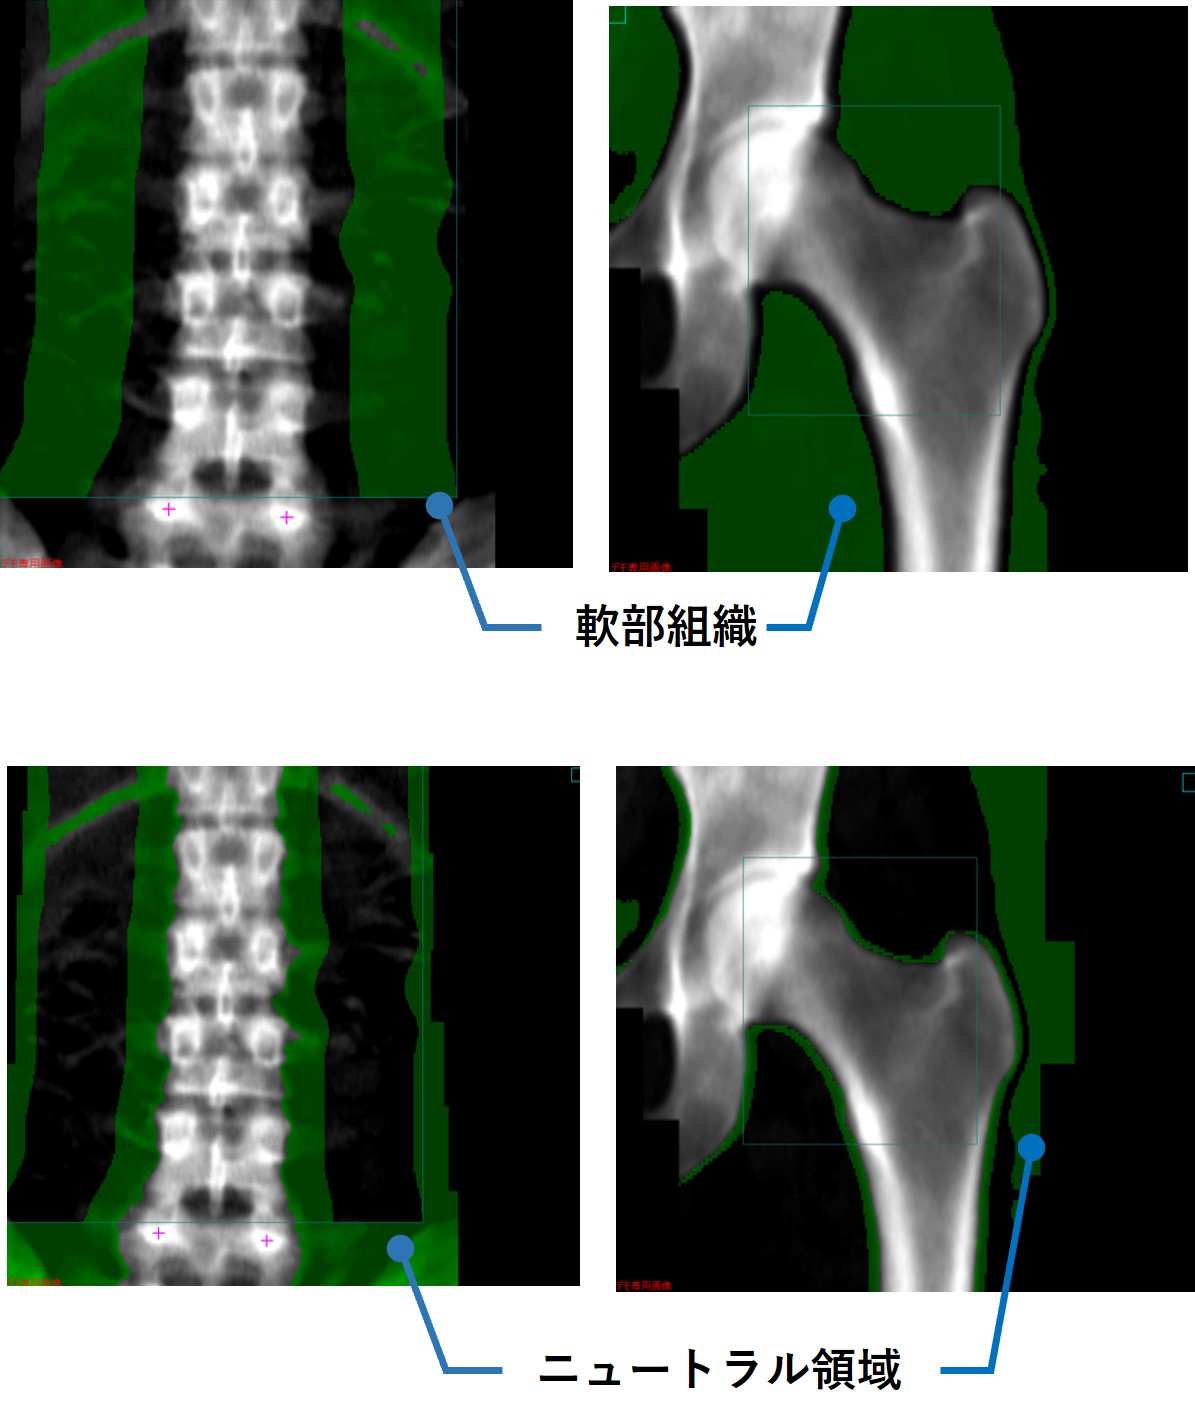

当院が使用しているGEヘルスケアの装置では、撮影範囲内に胆石等の極端に吸収値が異なる構造物が存在するとき、自動で「アーチファクト」として処理される。また、「骨領域」「軟部領域」だけでなく「ニュートラルポイント」という概念があり、骨量計算のうえで重要な機能だと感じている。これにより、腰椎横突起部など2次元画面上に軟部組織と骨が混在する部分や、大腿骨撮影範囲内の厚みが違う部分を計算から除外することができ、正確な検査の一助となっている。

Clinical Tips_yokohamashitobu04.jpg

軟部組織領域とニュートラル領域